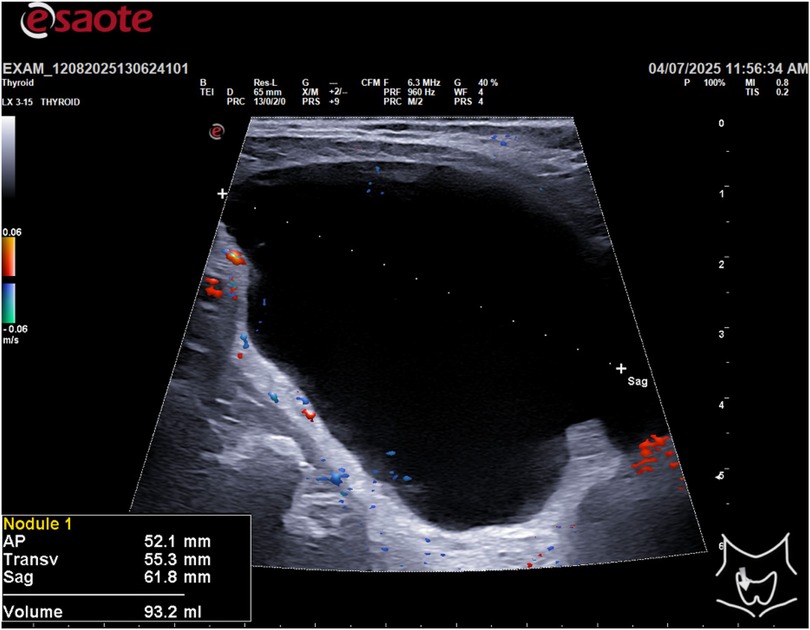

Following the ultrasound, an ultrasound-guided fine-needle aspiration (FNA) was performed on the cystic lesion (Figure 2). Approximately 90 ml of clear, “rock water"-colored fluid was aspirated (Figure 3). The cyst has been completely drained: AP 12.6 mm, Transverse 16.5 mm, and Sagittal 28 mm, for a calculated volume of 3.1 ml (Figure 3). The aspirated cystic fluid was immediately sent for biochemical analysis.

Figure 2

Ultrasound scan of a thyroid gland showing a dark region on the right, indicating potential abnormalities. The image includes indicators and measurements in the margins, typical of medical imaging.

Figure 2. Ultrasound-guided fine-needle aspiration (FNA).